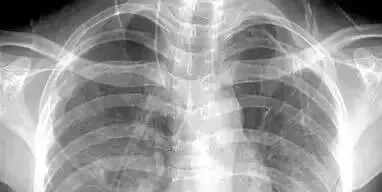

DR,通俗讲就是数字化X射线照相,X线穿过人体,由于不同组织的密度差异,对X线的阻挡程度不一样,成像的亮度也就会不同,最终形成明暗对比的图像。

同时,DR只能提供平面影像,就像一片面包,鼓的时候是看不清里面的纹路,一旦压扁里面的纤维一清二楚。同理,DR检查就像是把我们的骨头压扁一样去看,可以清楚的看见里面丝丝缕缕的东西。

胸部:粗看DR平片,细看CT

DR胸片可粗略检查肺、心影、主动脉弓、肋骨等,也可以检查有无肺纹理增多、肺内较大肿块、主动脉结钙化等。胸部CT检查显示出的结构更清晰,对检出胸部病变敏感性和准确性均优于常规DR胸片,特别是对于筛查早期肺癌有重大意义。而核磁共振成像对于肺内疾病的诊断,应用非常有限。